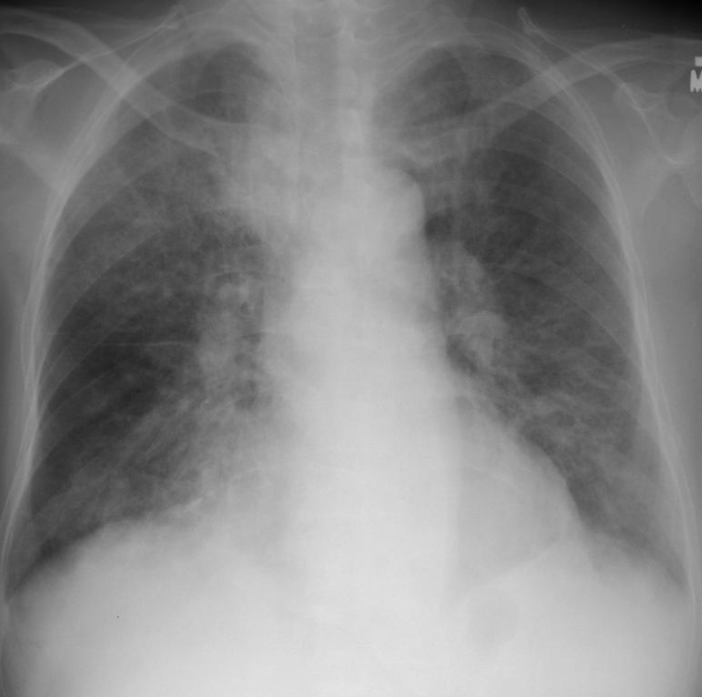

Pneumocystis

Pneumocystis cysts (silver stain)